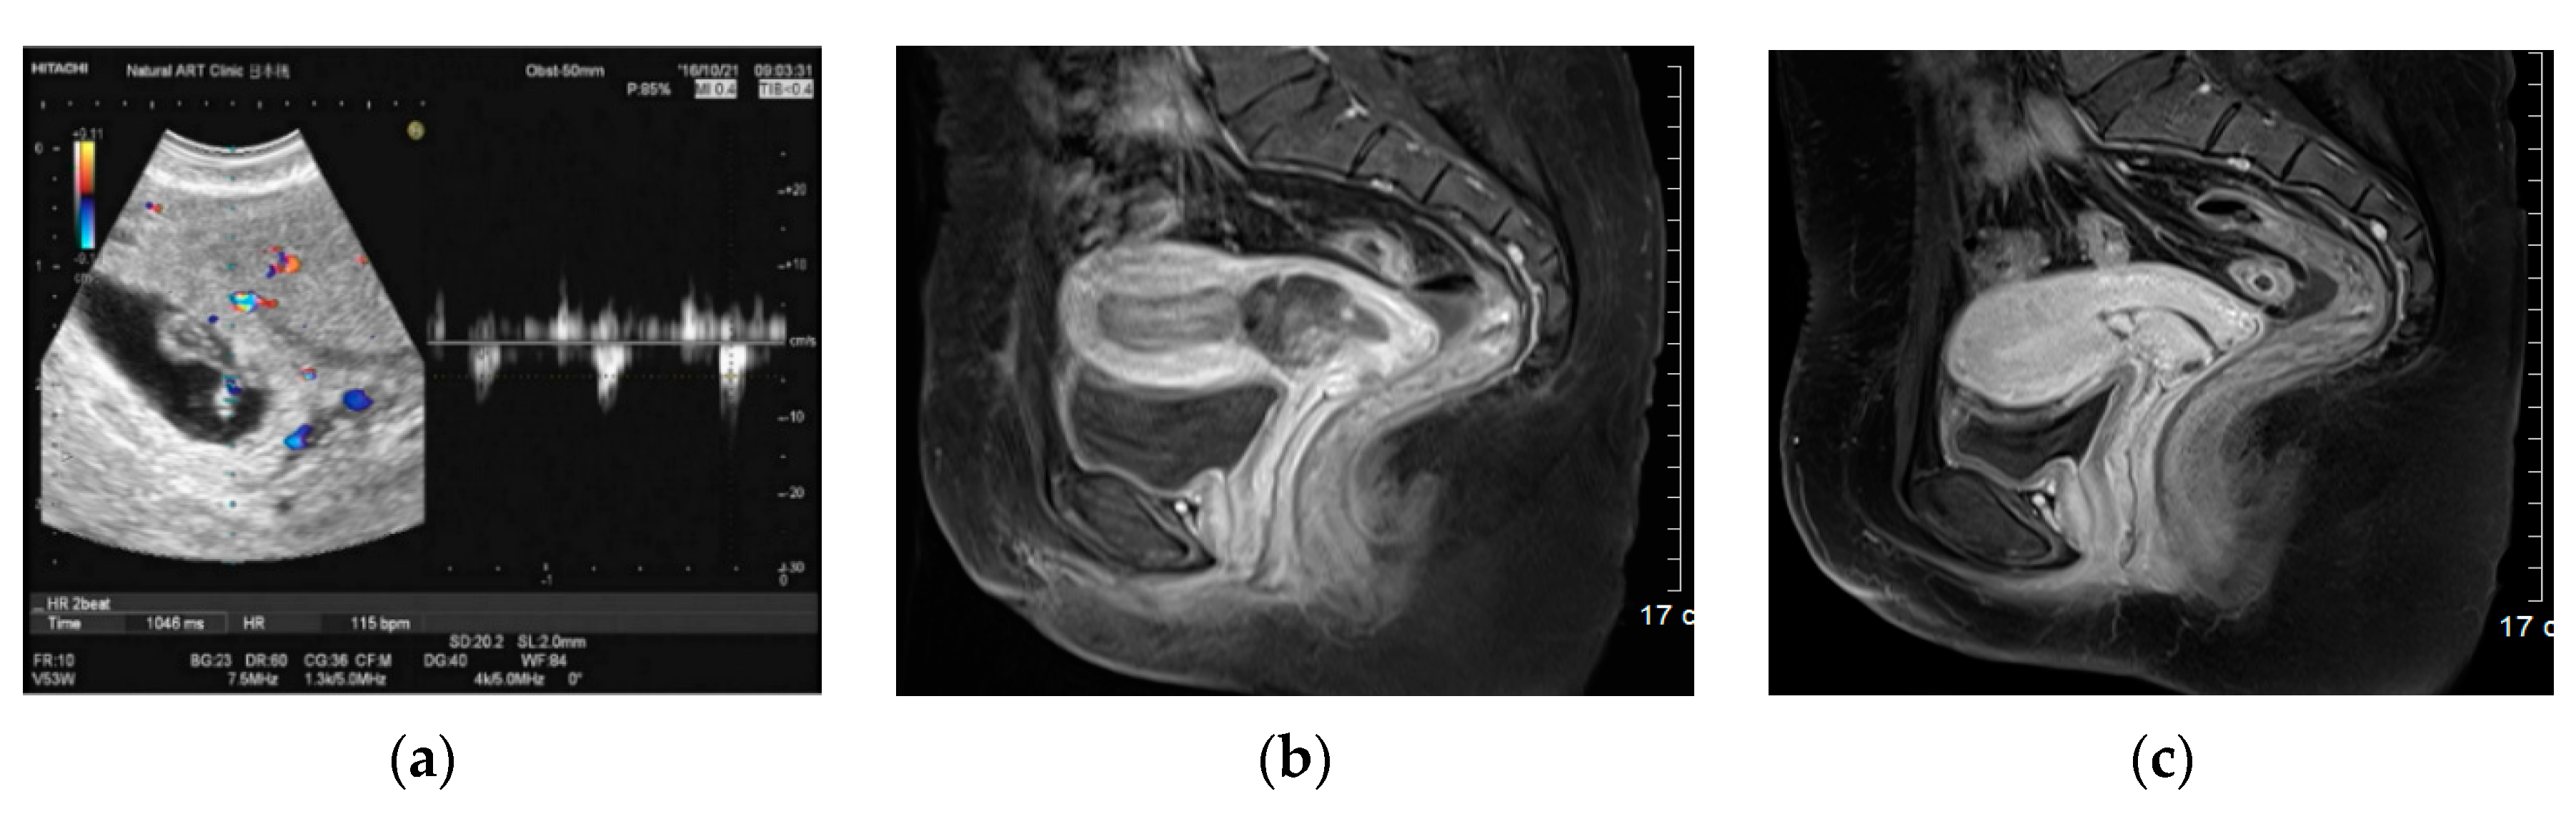

Figure 2.

Transvaginal ultrasound Doppler image and pelvic MRI scan of cesarean section scar pregnancy with positive fetal heartbeat. (a) Transvaginal ultrasound Doppler image demonstrating FHB-positive CSSP. (b) Axial sections of pelvic MRI before the injection; initial serum β-hCG level was 43,596 mIU/mL and that at 2 h after the AE injection was 32,161 mIU/mL, demonstrating a reduction rate of 26.2%. (c) Axial sections of pelvic MRI on day 25 of the injection. Serum β-hCG level was 6.8 mIU/mL (on day 38, the level decreased to < 1.0 mIU/mL).